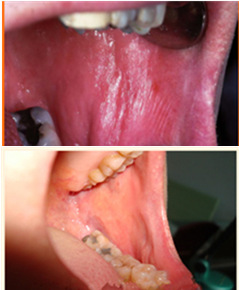

1、产生热能效应,改善血液循环,促进黏膜修复

2、清除局部炎症细胞,加速病损愈合<1ML

3、在表面坏死组织产生汽化、凝固,达到消炎止痛作用